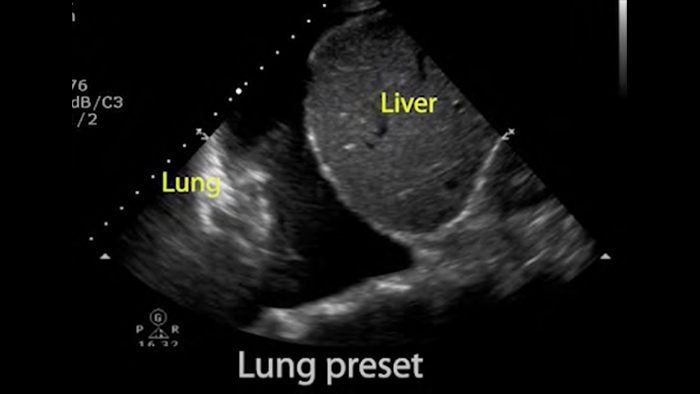

Utilice Lumify para la evaluación de las vías respiratorias y pulmonares

Las soluciones Lumify POCUS pueden ayudarle a detectar el tubo endotraqueal dentro de la tráquea, ayudar en los procedimientos de cricotirotomía emergentes, en el diagnóstico de derrame pleural y enfermedades alveolares intersticiales.

• Rango extendido de frecuencias de operación de 4 a 1 MHz • 2D, Doppler a color, Modalidad M, XRES avanzado e imágenes armónicas multivariables • Imagenología de alta resolución para aplicaciones abdominales y cardíacas: optimizaciones de preajustes de imágenes cardíacas, gineco-obstétricas, pulmonares, abdominales y FAST.